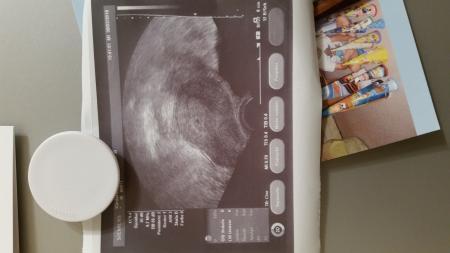

Hey ihr lieben.. Gestern War meiner erster Termin. . Bluttest wurde sofort positiv. . Und auf dem US Bild konnte man schon was sehen. Ein kleiner schwarzer Krümel Morgen muss ich noch mal hin.. bin nämlich ab Samstag 2 Wochen im Urlaub. Lg

Bild zu 1. Ultraschall Termin 5. Woche - Schwanger - wer noch? Rund um die Schwangerschaft

Sie will nur sicher gehen sie sagte es müsste morgen bissl größer sein. Ich bin zwei Wochen in Thailand.. deswegen denke ich. Sie sagt aber es sieht alles gut aus würde auch eine eileiter Schwangerschaft ausschließen.. sie ist halt bissl ängstlich Ich mein man sieht ja eine kleine fruchthöhle..